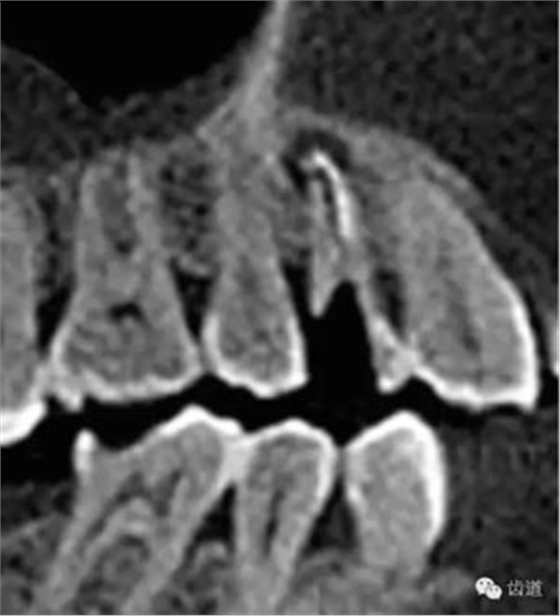

處理:顯微根管治療。放置橡皮障,去除暫封,顯微鏡下超聲去除頰側(cè)根管上段部分牙本質(zhì),探及遠(yuǎn)中根管口,見(jiàn)有糊劑遮蓋。Pathfile根管疏通,MTwo根管預(yù)備至2506#,配合3%次氯酸鈉和17%EDTA超聲蕩洗,干燥根管,放置氫氧化鈣糊劑,zoe暫封。

處理:放置橡皮障,去除暫封,超聲結(jié)合2%CHX清除遠(yuǎn)頰根管內(nèi)氫氧化鈣糊劑,主牙膠試合后95%酒精沖洗干燥根管,結(jié)合AHPlus糊劑連續(xù)波熱牙膠垂直加壓充填根管,樹(shù)脂分層粘接修復(fù)牙體。建議定時(shí)復(fù)診進(jìn)行嵌體修復(fù),患者未執(zhí)行。